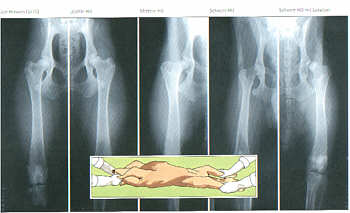

Einteilung der Hüftgelenkdysplasie

(von links nach rechts)

HD frei, HD-Grad A;

Nobergwinkel >/=105° ;

Keine Knochenveränderungen.

HD verdacht, HD-Grad B

Nobergwinkel >105° ;

Minimale Knochenveränderungen.

Leichte HD, HD-Grad C

Nobergwinkel >/=100° ;

Leichte Knochenveränderungen.

Mittlere HD, HD-Grad D

Nobergwinkel >/=90° ;

Mäßig-starke Knochenveränderungen.

Schwere HD, HD-Grad E

Nobergwinkel >/=80° ;

Massive Knochenveränderungen.

Winkelmessung nach Norberg

Mittels einer Schablone mit Kreisen werden die Mittelpunkte der Oberschenkelköpfe ermittelt und durch eine Linie verbunden. Durch die Mittelpunkte wird dann je eine Linie an den vorderen Pfannenrand gelegt. Der Winkel zwischen Verbindungslinie und der Linie am vorderen Pfannenrand (Doppelpfeil) wird gemessen.

Röntgenbilder von Hüftgelenken zur Diagnose der Hüftgelenkdysplasie (HD)

Das eingeschobene Bild zeigt die dazu erforderliche Lagerung des Hundes auf dem Röntgentisch. Voraussetzung hierfür ist eine spezielle Narkose.

Von links nach rechts.

HD frei; Leichte HD; Mittlere HD; Schwere HD; Schwere HD mit Luxation.